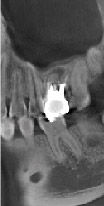

High resolution, 125 µm voxel images provide a clear observation of the periodontal pocket, the periodontal membrane, and the alveolar bone, as well as soft tissue such as the maxillary sinus membrane. A special dose reduction mode lowers exposure for soft tissue which reduces dosage to a mere 60% of the standard mode.

Multifunctional, it also offers panoramic and cephalometric imaging. With a total of 6 fields of view, 3D R100 is ideal for implantology as well as being suitable for periodontology, orthodontics, endodontics, oral surgery, and general dentistry.